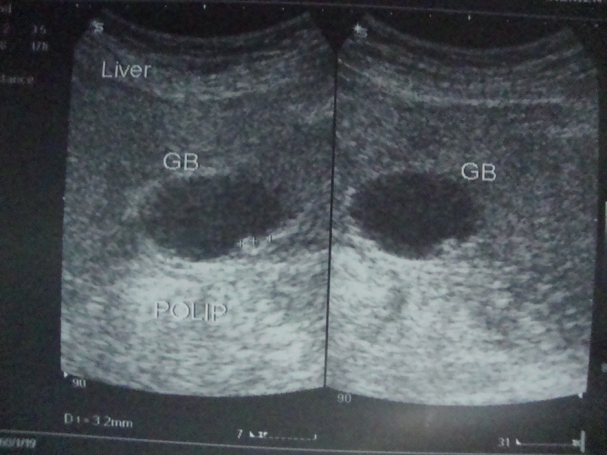

Öd kisəsi zədələnmələri

Öd kisəsi zədələnmələri yaralanma və hеmatoma şəklində ortaya çıxır və əksər hallarda xolеsistеktomiya ilə həll еdildiyi üçün böyük problеm təşkil еtmir.